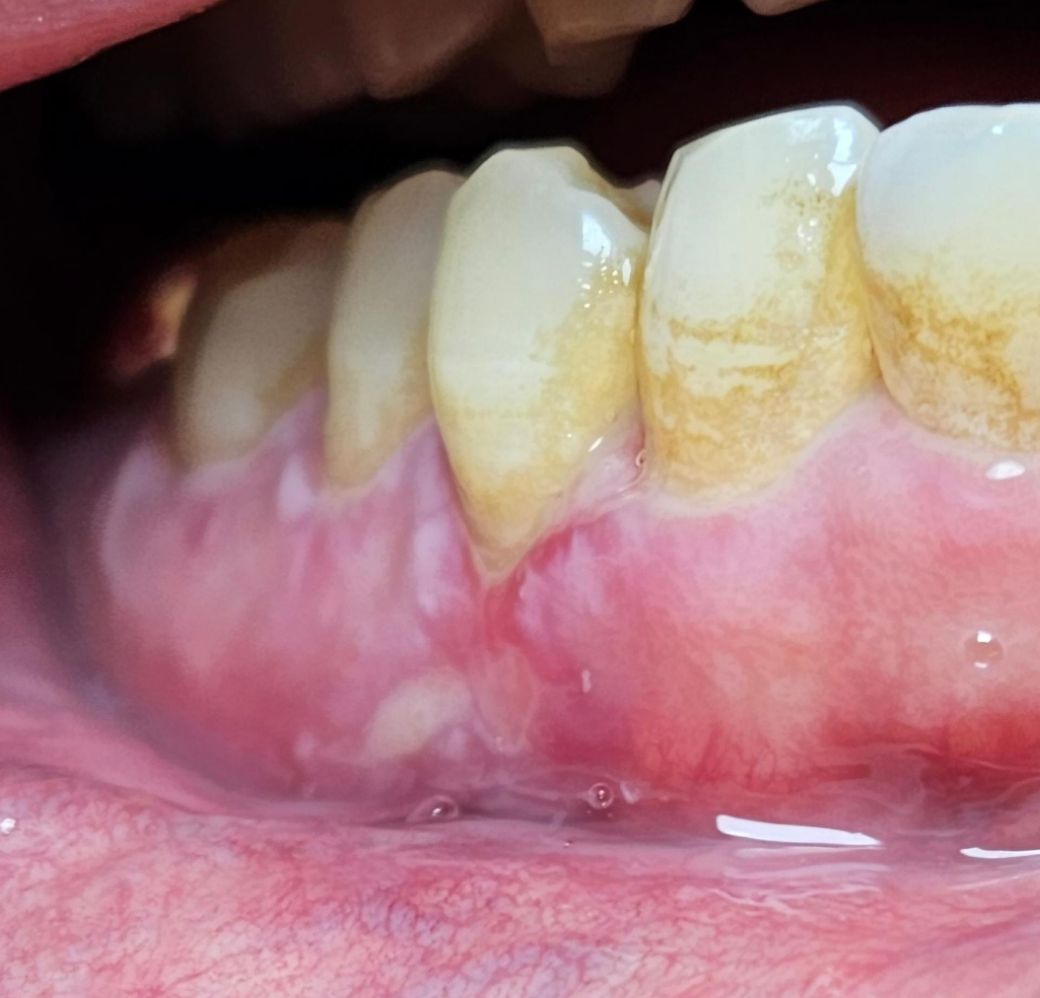

잇몸에 전반적으로 이러한 병변이 나타나고 있습니다

2개월정도 지속이 되고 있고 통증과 양치질할때 출혈이 나타나고 있습니다 치과에서는 면역력 문제라고 하는데 다른문제가 있는건 아닐까요?

• 2번 째 사진